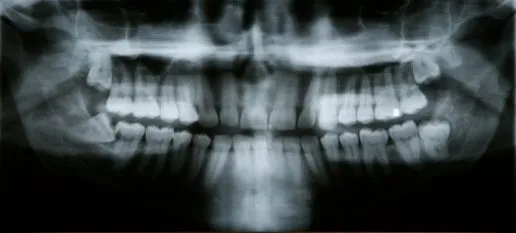

x-ray of mouth

A tooth becomes impacted when there is not enough room to accommodate the space in the dental arch and growth becomes impossible. After surgery to remove an impacted tooth, mild discomfort and some swelling is expected. This is part of the process and should not alarm you. You may use cold compresses to alleviate the swelling. In addition, your doctor will prescribe pain medication, which should be taken as directed. Patients are also advised to favor the extraction area and modify their diet for a few days to allow for healing.